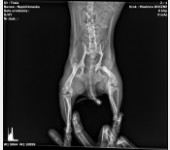

W niedzielę 12-05-2024r została potrącona. Od razu udaliśmy się do weterynarza, przebadał ja podał przeciwbólowe i przepisał kolejne. Lecz nic się nie poprawiło więc musieliśmy udać się na RTG . Niestety diagnoza nie zaciekawa bo okazało się że moja księżniczka ma złamaną kość w dwóch miejscach przy miednicy jak widać powyżej na zdjęciu. Niestety w naszej okolicy, nie wykonują takich operacji i dostałam wiadomość z punktami gdzie mogą wykonać taki zabieg i jakie idą koszty za tym.

Koszt operacji mojej Perełki to 5000PLN ( pięć tysięcy złotych ).